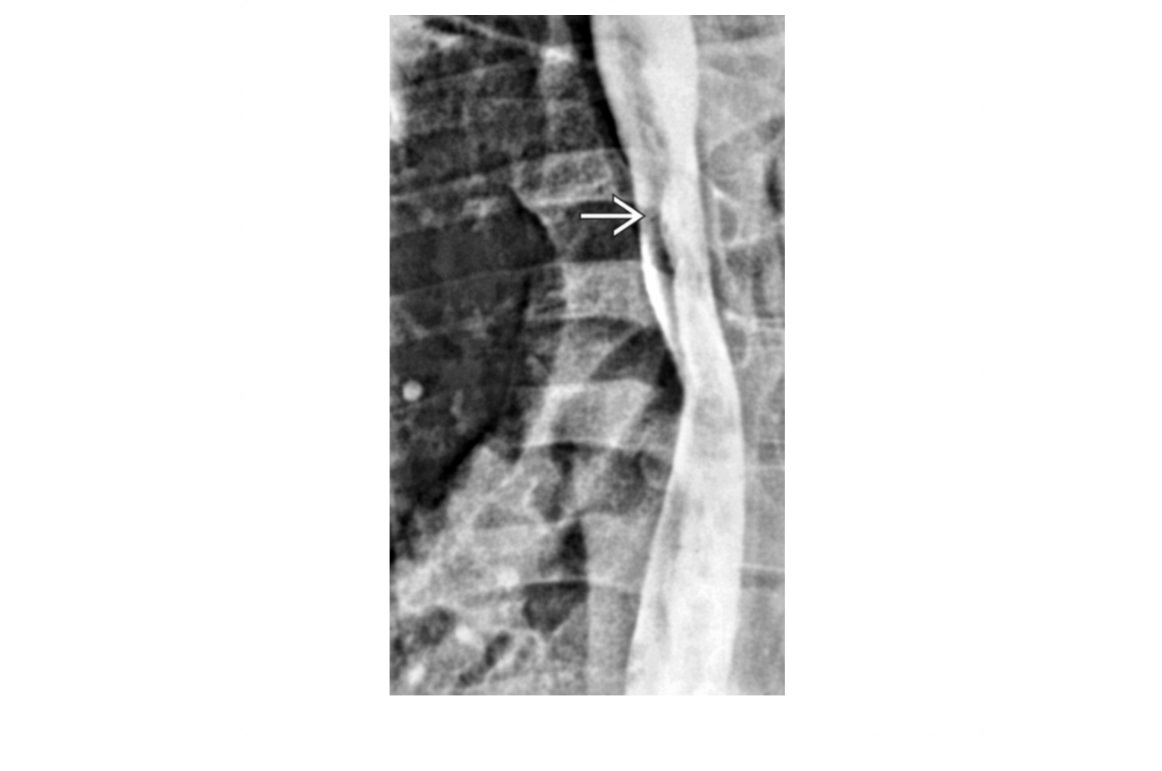

CT enterography features of active Crohn’s disease

**mucosal hyperenhancement **- most sensitive indicator but seen in other bowel diseases most specific sign for chrons - **Prominence of the vasa recta adjacent to the inflamed loop of bowel (comb sign) along with increased mesenteric fat attenuation** wall thickening (thickness >3 mm) CT enterography to depict extra-enteric disease/complications including -obstruction -sinus tract -fistula and abscess formation long-standing/inactive features include -submucosal fat deposition -pseudosacculation -surrounding fibro-fatty proliferation -fibrotic strictures MR enterography and enteroclysis - MR enteroclysis was superior to MR enterography in demonstrating mucosal abnormalities. -MR enteroclysis better bowel distension but not necessarily better diagnostics -MR enterography is more acceptable to the patient than MR enteroclysis